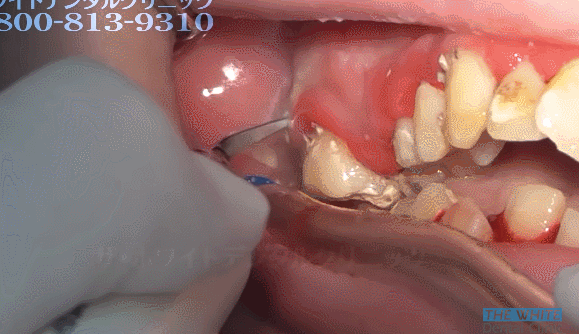

25세 여성의 치석제거. 분명히 난감이라고 말했습니다 (난감주의)

와우... 스케일링할때 피 엄청 나겠다

치아 제거 수준 ,,,

잇몸 진짜 다 내려앉겠다,,,

스켈링 4번에 나눠서 하셔야 할 각...

양치를 안하신건가? 저렇게 심각하면 진작 치과가시지 저정도면 바로 보일정도인데...

와... 치열 안좋아도 양치만 제대로 하면 안생기지 않나요...

치아 위에 잇몸도 치석때문에 부은건가요? 아파보여요 ㅠㅠ

저건.. 원장님이 큐렛도 해주셔야...ㅎㅏ...끔찍

저정도면 아프겠다

퉁퉁 부었네...아이고

충치 안생기나요??????

아우,,, 하시는 분 손목 나가시겠는데요,,,

헐 저정도로 깊게 많이 생기면 오히려 치과에서 하지 말라고 권장하지 않나요ㅜㅜㅜㅜ 잇몸 다 상할텐데..

입냄새 대박이었을거같아요...

거의 치아 옆에 치아 난 느낌

근데 어떻게 해야 저정도까지 치석이 쌓일 수 있는거에요 ?

저정도면..치조골 완전...와우....